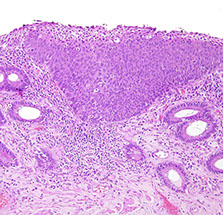

Solitary Rectal Ulcer Syndrome

Haphazardly arranged benign colonic crypts

Inflammatory Cloacogenic Polyps

Mucosal prolapse polyps. A, Inflammatory (cloacogenic) polyp of the anorectal transition zone. B, Strands of thickened and splayed muscularis mucosae extend around the crypt bases and into the overlying lamina propria. The crypts assume an angulated and distorted appearance. C, When embedded tangentially, prolapse polyps show strands of smooth muscle that appear to encircle colonic crypts, which frequently assume a “diamond” shape. D, On the surface, mucosal prolapse polyps often contain markedly regenerative, serrated/hyperplastic-appearing epithelium and ischemic-type changes with erosion. [2]